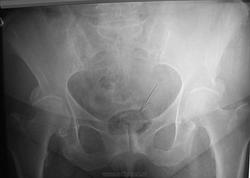

Пожилая женщина 78 лет, пришла на обследование ТБ суставов. Меня заинтересовало помимо артроза дополнительная тень в проекции мочевого пузыря. Может ли так выглядеть камень?

3. ТАКАЯ тень никогда не может быть камнем мочевого.

4. Согласен с Петровичем по поводу лампы в негатоскопе...хотя....не исключаю и неверную центрацию трубки )))))

А я бы однозначно рекомендовал Клизму. Пациенту перед контрольной рентгенограммой. И ещё кое-кому, чтобы думали о людях и технике с заботой и ответственностью. И вообще думать полезно. Перед тем как давать рекомендации, например. А лампу в негатоскопе заменить давно пора. Если же центрация трубки НАСТОЛЬКО неверная, обойтись лишь клизмою никак невозможно!

Надо заметить, что, по большому счёту, почти всегда "предисследовательская подготовка" пациентов желает быть более качественной.

На фоне каловых масс очень проблемно "ковырять скиалогию".